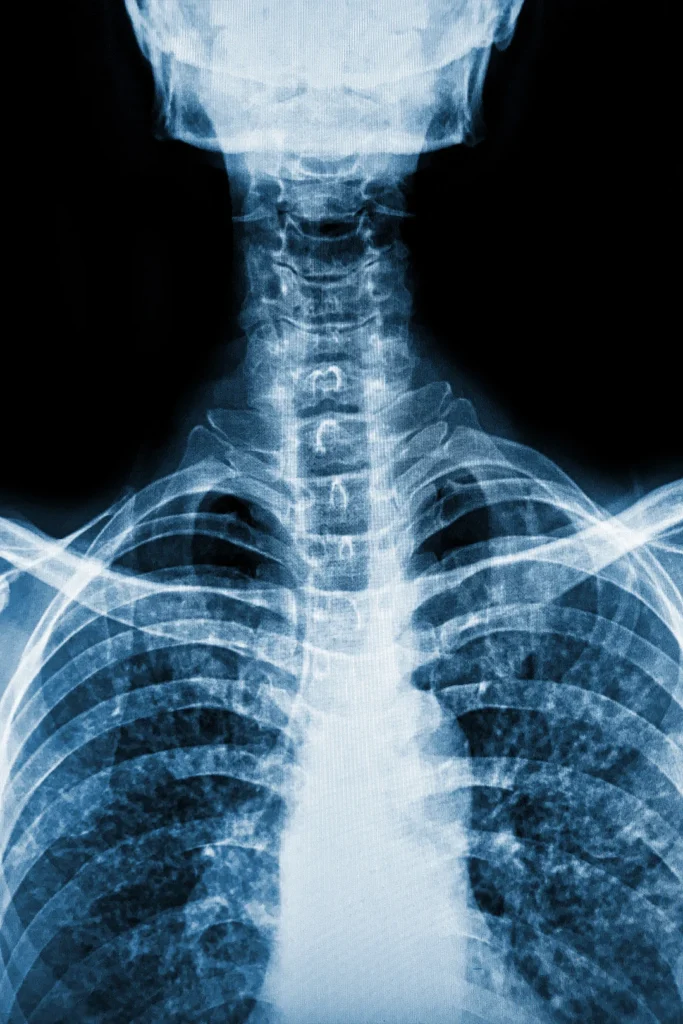

Digital X-ray imaging is a fast, safe, and non-invasive way to capture detailed images of your bones and joints. At our office, we use this technology to assess spinal alignment, detect injuries, and guide your personalized treatment plan with precision.

Unlike traditional film X-rays, digital imaging provides high-resolution images instantly and with lower radiation exposure. After capturing your images, we’ll review them with you and explain exactly what we’re seeing — so you understand the “why” behind your pain or dysfunction.

Clear imaging helps us identify misalignments, degenerative changes, disc issues, and other underlying conditions that may not be visible through a physical exam alone. With this insight, we can make more informed decisions about your care, track your progress over time, and ensure you’re getting the most targeted, effective treatment possible.